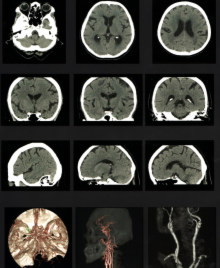

<CT>

頭部 単純CTおよび造影CT

3DCTおよび3DCTA

<MRI>

頭部 T1画像、T2画像

FLAIR画像

Dw画像、ADC画像

T2*画像

脂肪抑制画像

MRA画像(3D画像)

造影MRI